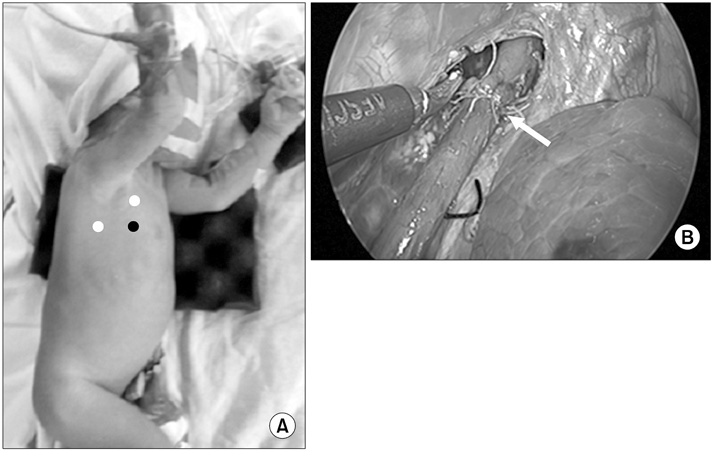

Esophageal atresia (EA) with tracheoesophageal fistula. (A) Position of patient for operation of EA (white dots, working port; black dot, camera port). (B) After ligating azygos vein, fistula was also ligated with simple suture, and end-to-end anastomosis of esophagus was done with interrupted suture. Arrow, end-to-end anastomosis site.

Fig. 1 Esophageal atresia (EA) with tracheoesophageal fistula. (A) Position of patient for operation of EA (white dots, working port; black dot, camera port). (B) After ligating azygos vein, fistula was also ligated with simple suture, and end-to-end anastomosis of esophagus was done with interrupted suture. Arrow, end-to-end anastomosis site.